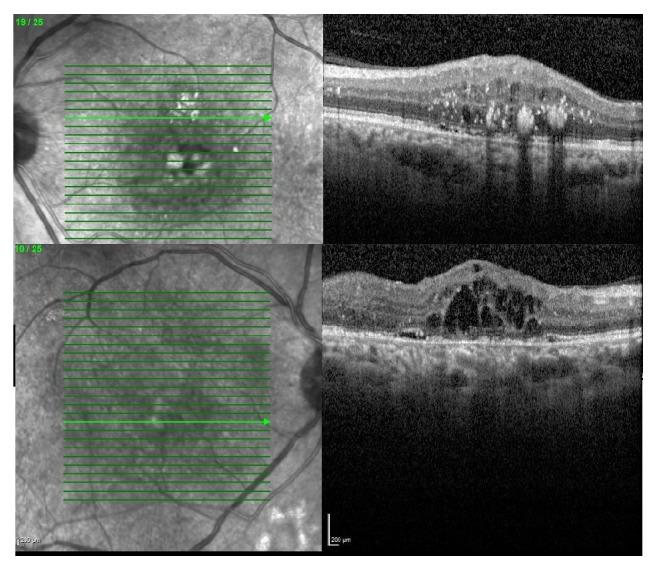

Dexamethasone implant, 0,7 mg (Ozurdex, Allergan, Inc., Irvine, CA, USA), is drug mostly used in the treatment of the diabetic macular edema and edema related to retinal vein occlusion. By reporting this case we aimed to report a new side effect of 0.7 mg intravitreal dexamethasone implant that has not been reported in the literature before.

地塞米松植入剂,0.7毫克(奥助得,爱力根公司,美国加利福尼亚州欧文市),是一种主要用于治疗糖尿病性黄斑水肿及视网膜静脉阻塞相关水肿的药物。通过报告该病例,我们旨在报道一种0.7毫克玻璃体内注射地塞米松植入剂的新副作用,此副作用此前尚未见文献报道。